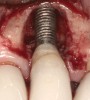

Fig 2. The height of this abutment was less than 2 mm on the facial. This may have led to additional marginal bone loss. Bacterial colonization of the abutment and the exposed implant body resulted in peri-implantitis.

Figure 2